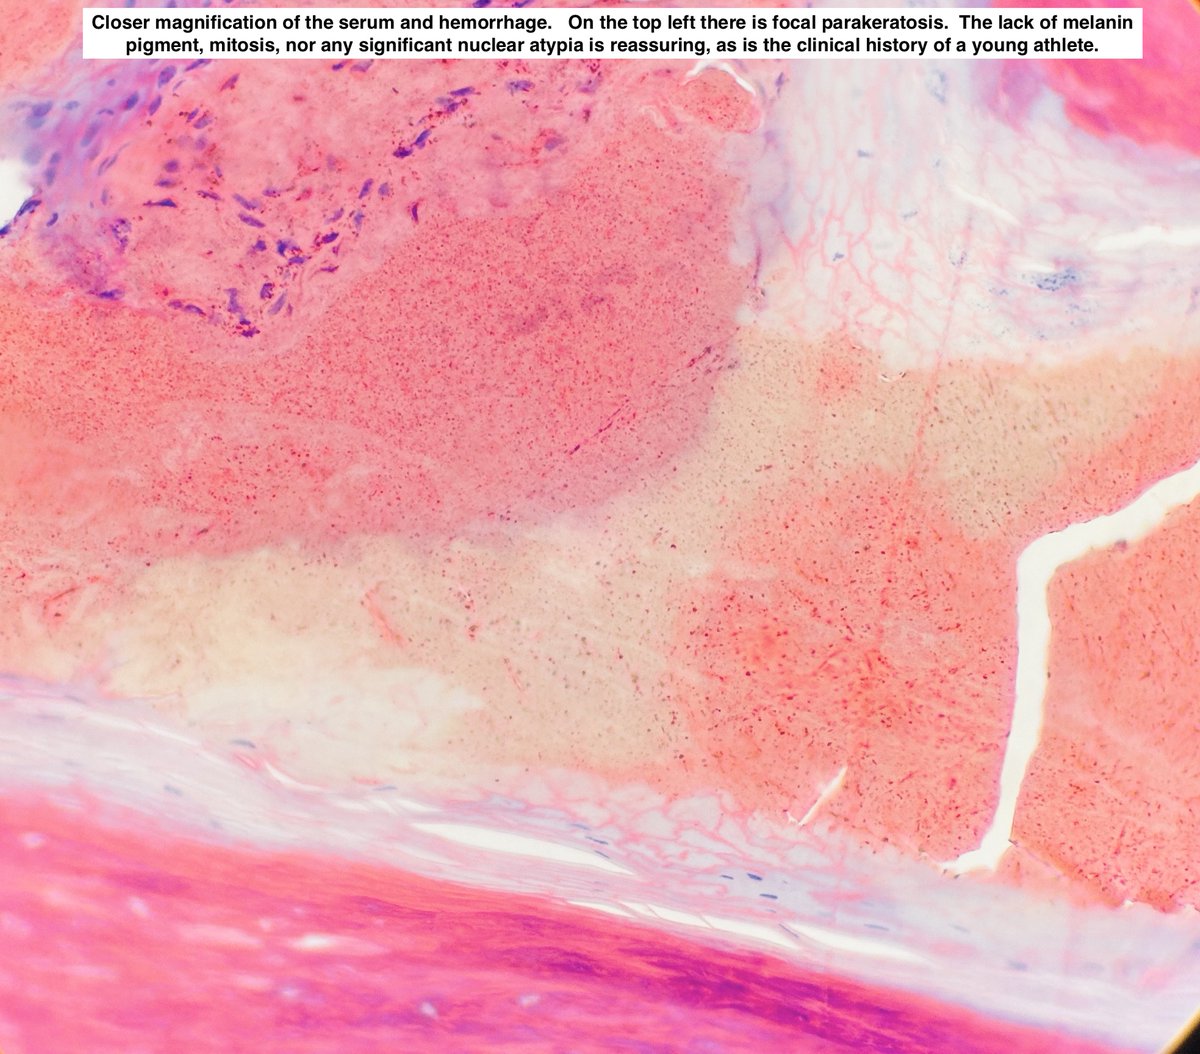

🩸 Talon Noir 📖 Benign ⚾️ 🏀 🏈 ⚽️ Often seen in athletes 🩺 Brown-black macules on foot, most commonly on heel ⚠️ May mimic melanoma 🔬 Acral skin, hyperkeratosis, hemorrhage in stratum corneum +/- telangiectatic vessels in papillary dermis #dermpath #fammed #path4people

📖 Benign

⚾️ 🏀 🏈 ⚽️ Often seen in athletes

🩺 Brown-black macules on foot, most commonly on heel

⚠️ May mimic melanoma

🔬  Acral skin, hyperkeratosis, hemorrhage in stratum corneum +/- telangiectatic vessels in papillary dermis